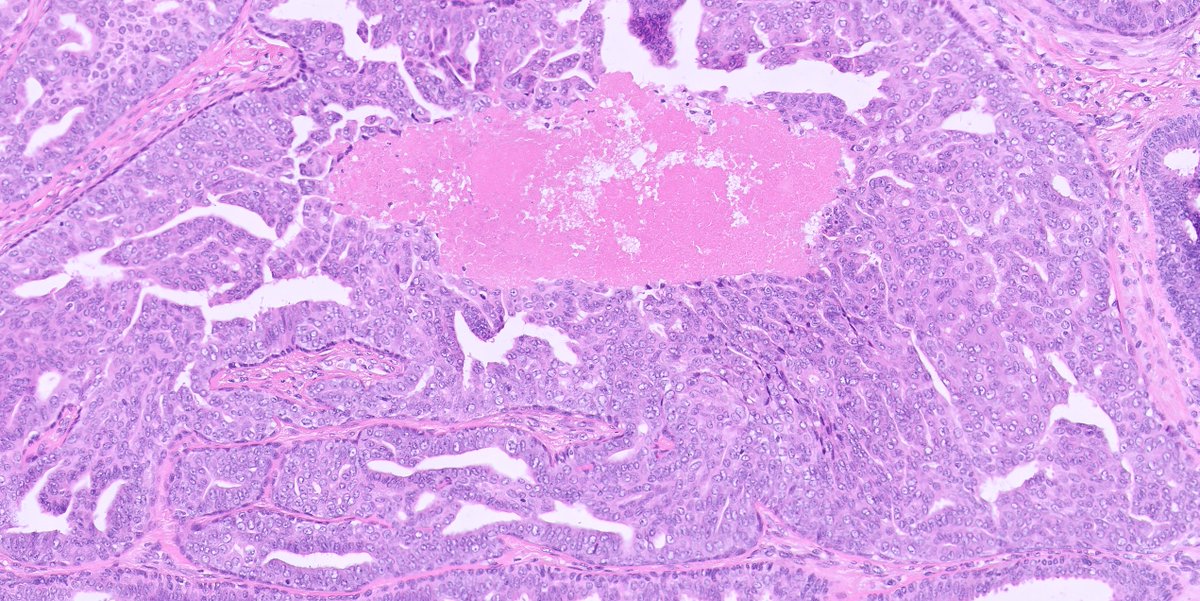

Metastatic renal cell carcinoma is really a sneaky thing. This example produced a duodenal submucosal lesion - at first glance it resembles Brunner glands. #UMiamiPath Modern Pathology Innovative Science Press

Metastatic renal cell carcinoma is really a sneaky thing.  This example produced a duodenal submucosal lesion - at first glance it resembles Brunner glands. #UMiamiPath <a href="/ModernPathology/">Modern Pathology</a> <a href="/science_press/">Innovative Science Press</a>